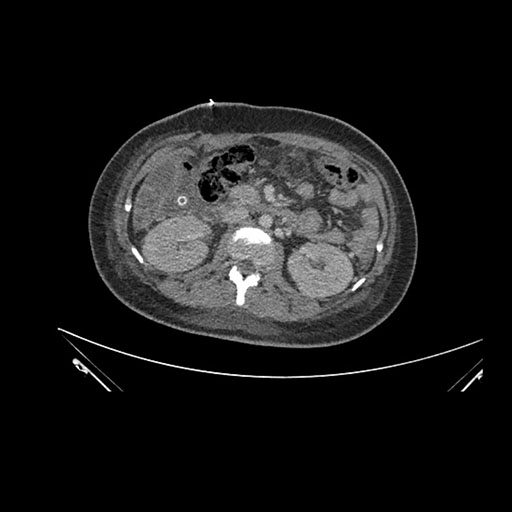

Imaging Analysis

Look through the patient's CT scan to identify any areas of concern for the necessary procedure.

Coronal Venous

Based on initial findings, which issue(s) would you be most concerned about?